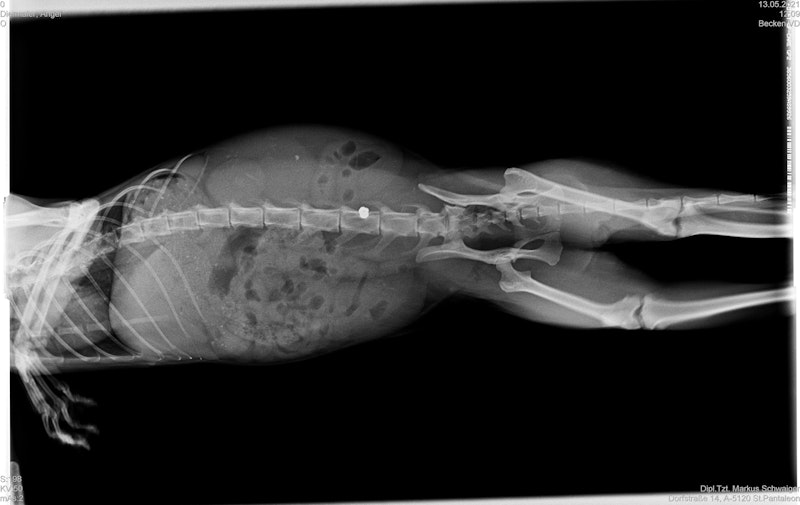

Die kleine "Angel" wurde offenbar von einem Tierhasser mit einem Luftdruckgewehr angeschossen. Das Projektil steckte genau im Bereich ihrer Wirbelsäule – "Heute" berichtete.

Die schwarze Katze müsse schnellstmöglich operiert werden, weil es sonst zu einer Verschlechterung des Zustandes kommen könne und dadurch ernste Probleme bei der Geburt von Angels Babys und bleibende Schäden zu befürchten seien.

Gleich am Donnerstag früh wurde der Stubenpanther daher vom Pfotenhilfe-Team nach Wien gebracht und umfangreich untersucht. Eine Herausforderungen bei der Behandlung war die Narkose, diese musste genau gesetzt werden, damit die Babys keinen Schaden erleiden.